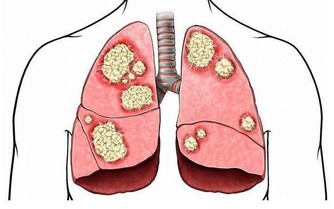

特別是初春,天氣由寒轉暖,各種致病的細菌、病毒隨之生長繁殖。

溫熱毒邪開始活動,現代醫學所說的流感、流腦、麻疹、猩紅熱、肺炎也多有發生和流行。

此外,注意口鼻保健,阻斷溫邪上受首先犯肺之路。